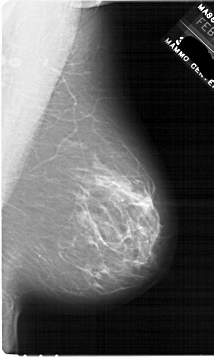

A_1763_1.RIGHT_MLO

RIGHT_MLO LINES 6766 PIXELS_PER_LINE 4051 BITS_PER_PIXEL 12 RESOLUTION 43.5 NON_OVERLAY